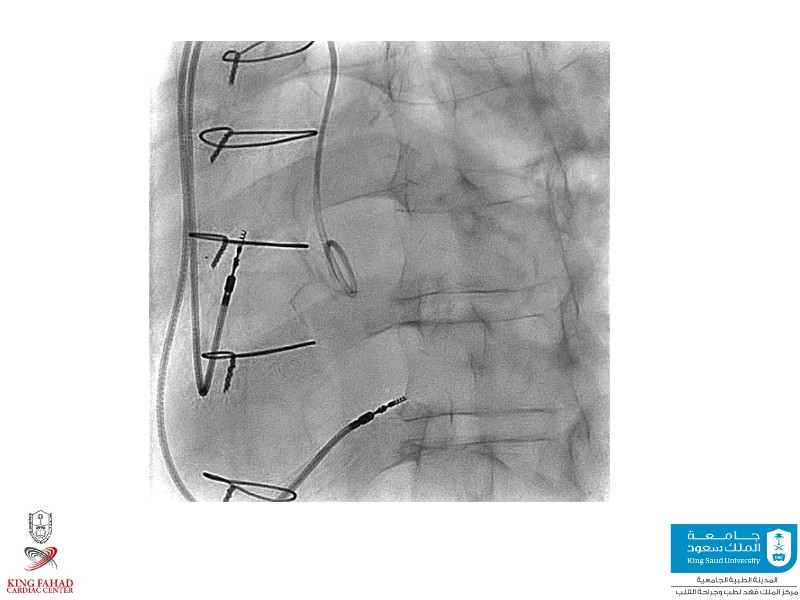

This session helps you anticipate and address complex scenarios such as mitral valve-in-valve, TAV-in-SAV, and valve-in-valve-in-valve procedures. Learn from expert case discussions that explore procedural strategies, technical challenges, and best practices to optimize outcomes in redo structural heart interventions.

- To anticipate and manage second valve scenarios with SAPIEN 3 Ultra RESILIA, including mitral valve-in-valve, TAV-in-SAV, and TAV-in-TAV

- To understand procedural strategies and challenges in complex redo scenarios using SAPIEN 3 Ultra RESILIA